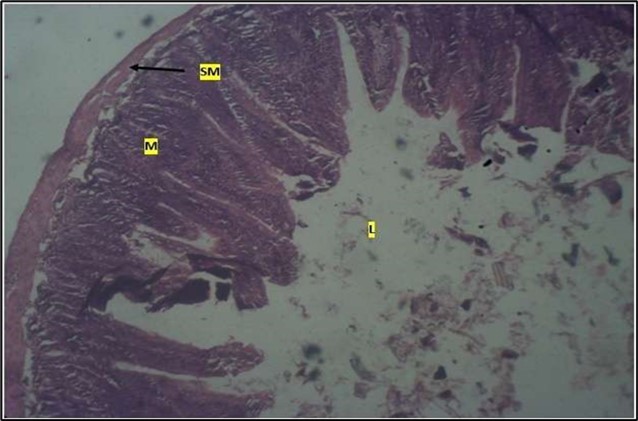

Histological examination of the small intestine result in control animals revealed a normal architecture with the red pulp and white pulp with no pathological observation Figure 2. Administration of Abelmoschus esculentus at low dose shows an increased cellularity with numerous cells in the Mucosa and the villi projecting towards the lumen. Focal metaplasia of mucosal cells alongside villous disruption was also observed (Figure 3). The high dose group showed normal cellular architecture with no villous disruption (Figure 4).

Figure 2.Control showing the mucosa with intestinal villi (v) projecting towards the lumen (l) and the underlying smooth muscle layer (sm) all appearing normal

Figure 3.Low dose showing numerous epithelial cells in the mucosa (m) with villi projecting towards the lumen (l). The is focal metaplasia of the mucosal cells with villous disruption. smooth muscle layer appears normal. H & E. X40